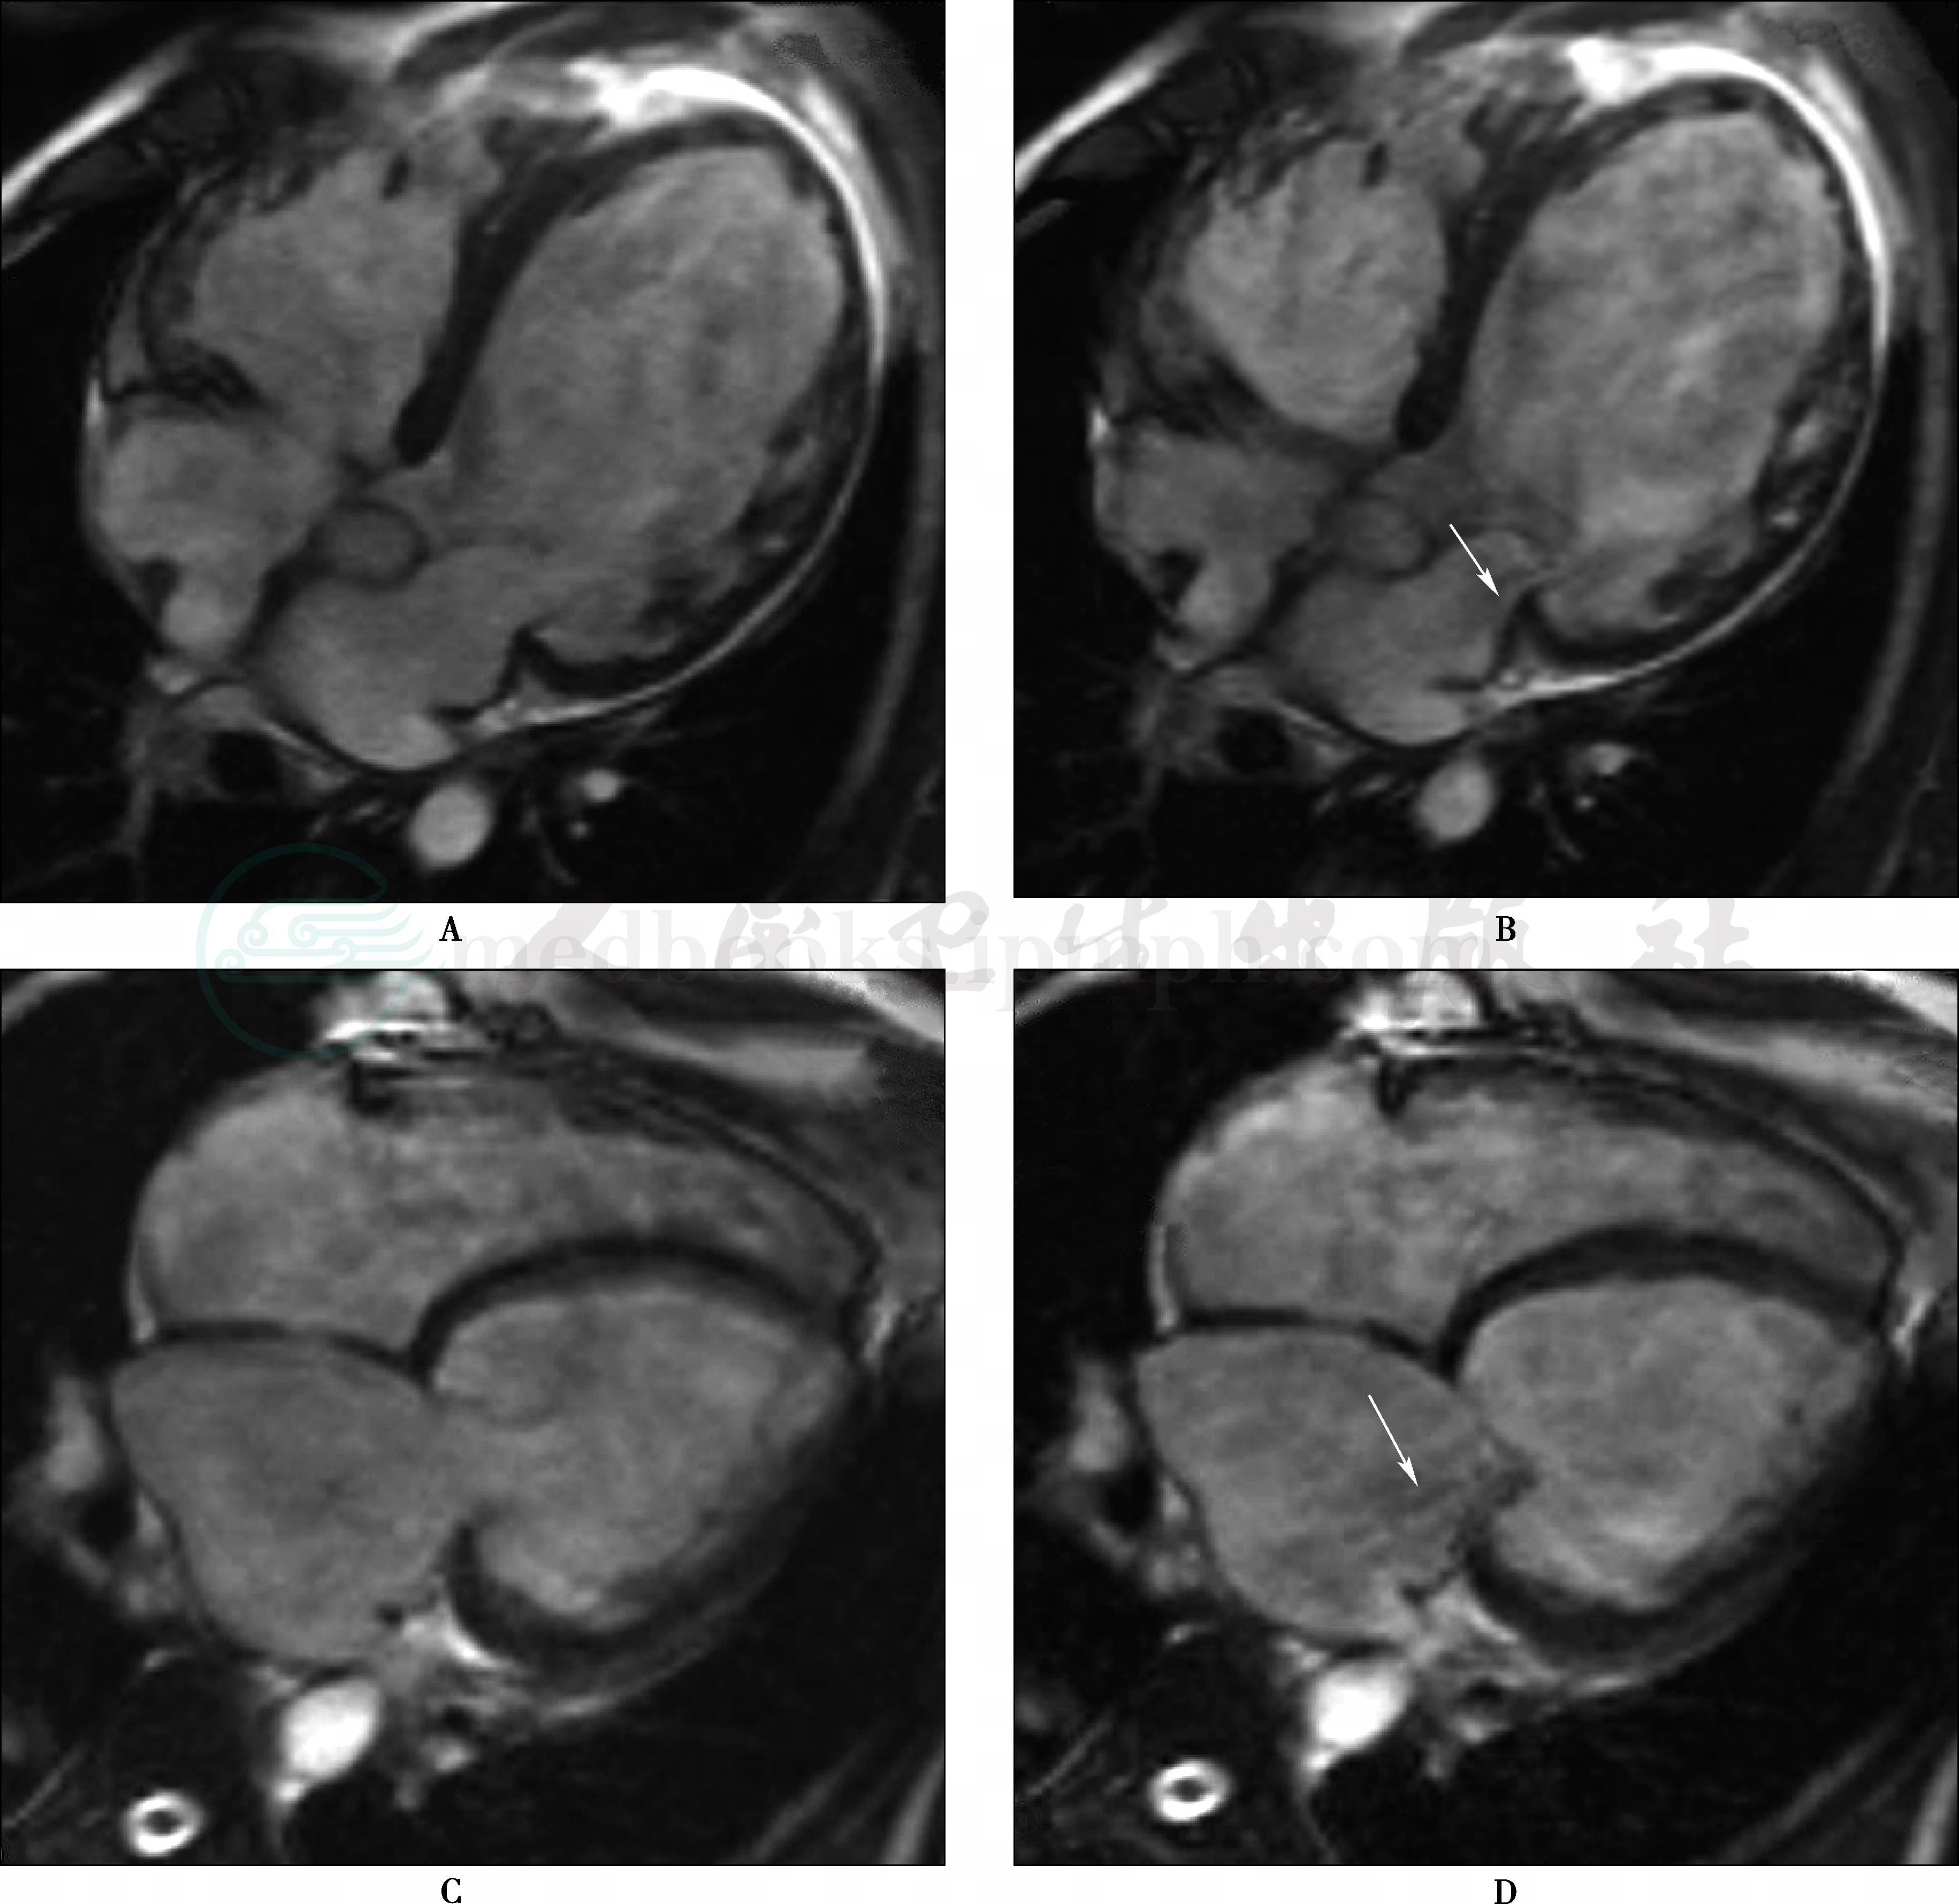

A、B.心脏MRI左室流入流出道:正常二尖瓣及主动脉瓣关闭与开放;C、D.心脏MRI四腔位:正常二尖瓣及三尖瓣关闭与开放

A、B.风湿性心脏病患者,MR电影收缩期显示二尖瓣口左房内可见反流现象,呈稍低信号(箭头);C、D.另一例风湿性心脏病患者,MR电影收缩期显示二尖瓣口左房内可见反流现象,呈稍低信号(箭头)

SE序列表现为左心房、左心室增大。Cine MRI心脏二腔位(右前斜位)示收缩期左心室血液经二尖瓣口向左心房喷射,呈条状低信号区。二尖瓣狭窄伴关闭不全时,MRI可同时显示相应的改变。

主要涉及心脏房室的射血功能、跨瓣压测定、反流量的定量等,MRI成像方式和评价能力在先天性心脏病章节已详细介绍,此处不再重复。但须补充的是在Cine MRI可通过测量血流信号缺失区的面积大小对瓣膜反流程度进行半定量评价。虽然所测结果与彩色多普勒测得结果相关系数高达0.74,可信度较高。但其固有的成像原理决定了其存在一定的缺陷,主要表现为:①信号缺失对应于涡流或杂乱血流区,其容积与实际反流容积并非完全一致;②瓣膜反流束在心动周期中为形态和方向不断变化的动态三维结构,多种因素(除反流容积外,跨瓣压、瓣口形态和面积、心室顺应性等)影响其空间分布,从而影响其测量结果:③梯度场强、翻转角等技术因素也影响反流束的大小和形态。对于瓣膜狭窄所致喷射血流导致的信号缺失亦可通过类似的方式测得,研究认为二尖瓣狭窄所致的信号缺失与多普勒测得的结果相关性良好。另外,Cine MRI能够提供更多的形态学和功能学信息,如确定房间隔的角度和运动轨迹以利于房间隔穿刺、二尖瓣球囊扩张术后心脏功能和血流动力学变化(图2~图4)。